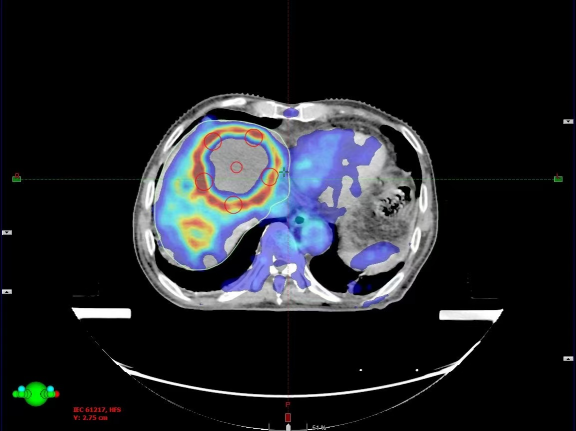

本次治疗的患者是一位结肠癌术后、靶向及化疗后出现肝转移的病人。针对其病情,选择了每次600cGy,总共五次的SFRT治疗方案,并同步应用了免疫疗法(PD-1抑制剂)。这种联合疗法不仅能精准打击肿瘤细胞,同时激活患者的免疫系统,进一步抑制肿瘤扩散。

在治疗过程中,使用TrueBeam平台的精密计划系统,确保了每一剂量都能够精准作用于肿瘤病灶,同时最大限度地减少了对正常肝脏组织的损伤。从治疗计划到实施,整个流程保持高水平的精度和稳定性。